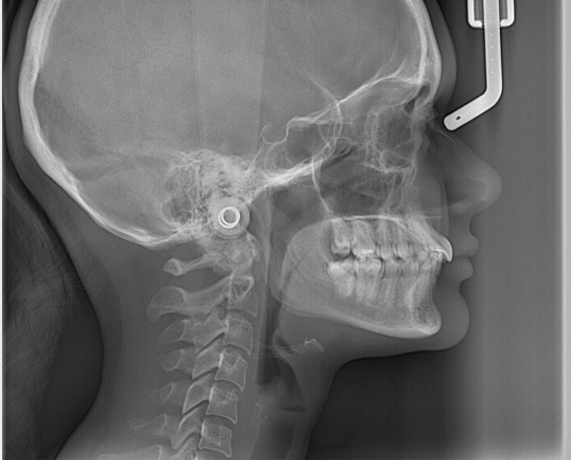

Clinical Findings:

- Mouth opening: 29 mm with leftward deviation

- Muscle tenderness: Masseter, temporalis, lateral pterygoids

- Bite: Deep bite, contributing to dysfunction

- TMJ clicking on the left side

- MRI: Bilateral Disc Displacement Without Reduction (DDwoR) and joint strain